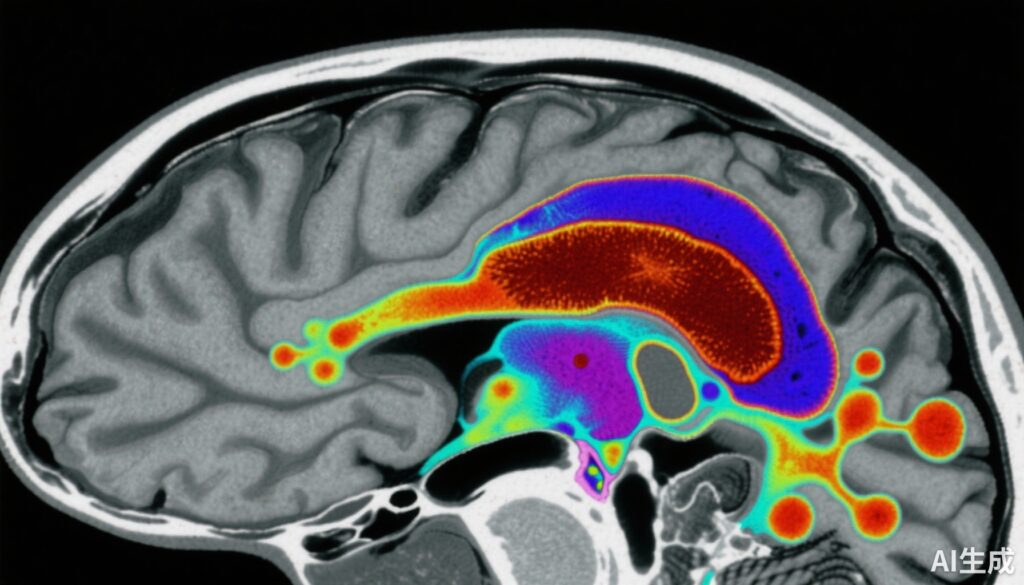

This case-control study involved 159 participants: 80 healthy controls and 79 individuals with early-course schizophrenia (including antipsychotic-naïve or antipsychotic-free patients). Magnetic susceptibility in the SN-VTA was quantitatively measured using quantitative susceptibility mapping (QSM) MRI, which provides a noninvasive marker of tissue iron levels.

Finally, in 40 patients with schizophrenia, dopamine synthesis capacity in the striatum was measured via [18F]-DOPA positron emission tomography (PET), enabling correlative analysis between SN-VTA iron content and dopaminergic activity.

1. Reduced SN-VTA Magnetic Susceptibility in Schizophrenia: Patients exhibited significantly lower QSM values in the SN-VTA (effect size d = -0.66, 95% CI -0.98 to -0.34) compared to controls. This indicates diminished brain iron levels in this critical dopaminergic region.

3. Inverse Correlation Between SN-VTA Iron and Striatal Dopamine Synthesis Capacity: In schizophrenia patients, lower magnetic susceptibility in SN-VTA was significantly associated with greater striatal dopamine synthesis (Ki cer) (correlation coefficient r = -0.44). This relationship remained significant after controlling for neuromelanin and myelin measures.

4. Regional Specificity: The most pronounced effects were localized to the ventral portion of SN-VTA, a region implicated in modulating striatal dopaminergic tone.